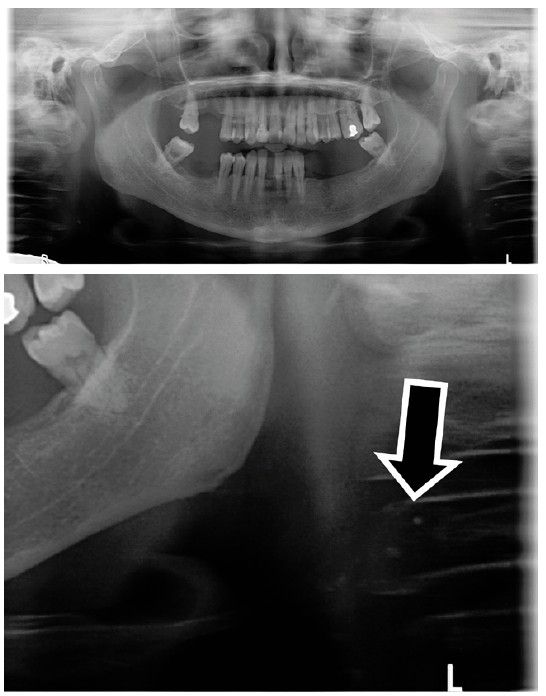

Paciente 1

Se presenta a una paciente de 75 años, con periodontitis estadio III generalizado, grado A. Ha sido tratada periodontalmente en nuestra consulta donde continúa realizando sus revisiones periódicas. En julio de 2022 acude a su cita de mantenimiento periodontal. Se le solicita una radiografía panorámica de control con el objetivo de evaluar la estabilidad de sus niveles óseos y descartar la presencia de caries u otras patologías bucodentales. La radiografía reveló la presencia de radio opacidades bilaterales de forma irregular, dispuestas de forma lineal y vertical en los tejidos blandos del cuello, por debajo del ángulo mandibular, entre la 3ª y la 4ª vértebra cervical (Figuras 1, 2 y 3). El diagnóstico radiográfico de presunción fue compatible con calcificaciones bilaterales de las arterias carótidas. En su historia médica la paciente refirió antecedentes familiares de Alzheimer, que no era fumadora, y que presentaba osteoporosis en tratamiento con denosumab en inyecciones subcutáneas cada 6 meses. Asimismo, mencionó que en algunas analíticas los niveles de colesterol habían estado algo elevados, aunque no pudo aportar más detalles ni resultados de las analíticas. No tenía prescrito ningún tratamiento específico para el colesterol y ocasionalmente tomaba Danacol®.

Fue remitida a su médico de atención primaria, explicando el hallazgo incidental en la radiografía panorámica, con el fin de que valorase la posibilidad de solicitar otras pruebas diagnósticas que pudieran confirmar la presencia de ateromas carotídeos. El médico le solicitó un eco-Doppler, donde se observaron varias placas de ateroma calcificadas situadas en la bifurcación de ambas carótidas y en el origen de las carótidas internas. Estas calcificaciones todavía no estaban produciendo estenosis hemodinámicamente significativas.

También se le solicitó analítica de sangre donde se observaron niveles elevados de colesterol, por lo que su médico le prescribió tratamiento con estatinas.

En esta paciente, el diagnóstico por parte de su médico fue precoz y anterior a la aparición de sintomatología gracias a la detección de las calcificaciones en una radiografía panorámica solicitada durante su mantenimiento periodontal.

Cuando son pequeñas tienen una apariencia radiográfica circular. Sin embargo, los grandes ateromas tienen forma lineal o rectangular delgada. En el paciente 1, las calcificaciones eran bilaterales, grandes, rectangulares, irregulares, situadas entre 1-2 cm posteroinferiores al ángulo mandibular, suprayacentes a los tejidos blandos prevertebrales. En el paciente 2, sin embargo, las calcificaciones aparecían unilateralmente, más pequeñas, circulares y múltiples, suprayacentes a los tejidos blandos prevertebrales y adyacentes al hioides.

En el paciente 1 y 3 las calcificaciones aparecían en la bifurcación carotídea, el lugar más frecuente de aparición, según Friedlander y Friedlander8. En los pacientes 2 y 3 los ateromas carotídeos eran unilaterales, izquierdo en el paciente 2 y derecho en el paciente 3, coincidentes con las imágenes calcificadas de manera unilateral que se habían observado en la radiografía panorámica solicitada únicamente por motivos de control periodontal.

Las calcificaciones pueden aparecer de manera unilateral o bilateral. Garoff y cols. en 201918 concluyeron que la aparición de calcificaciones bilaterales y con una forma que delinea los vasos, como en el paciente 1, son marcadores de riesgo independiente de futuros eventos cardiovasculares.